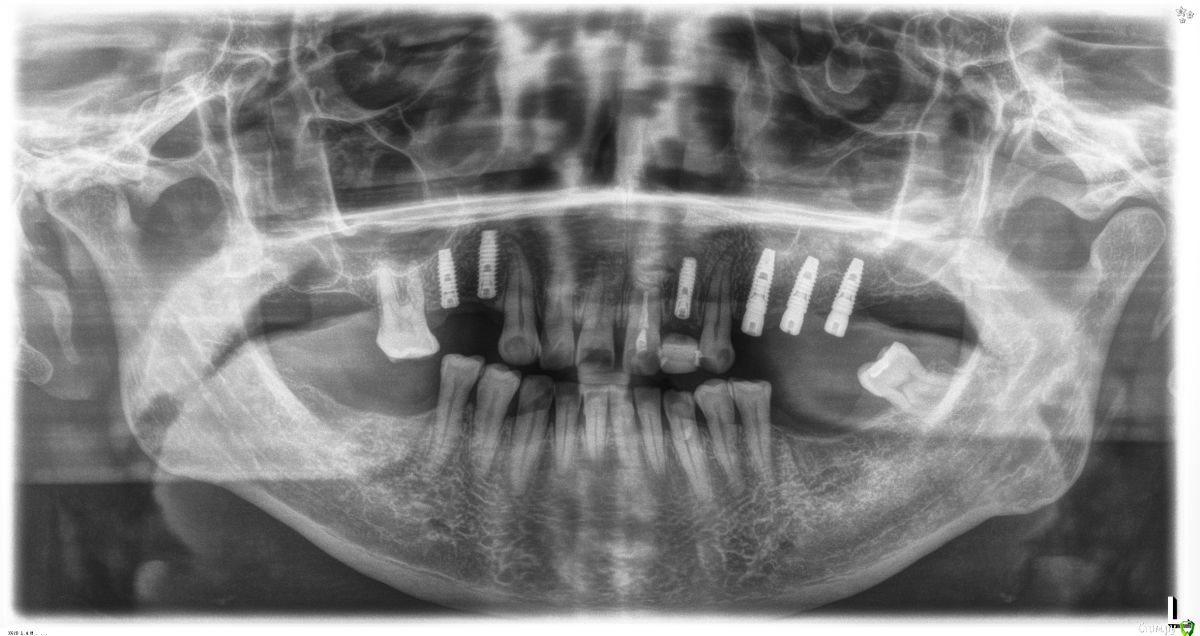

Fibez Опубликовано 8 апреля, 2016 Поделиться Опубликовано 8 апреля, 2016 Наклон мешает протезированию тем, что иногда трансфер упирается в зуб. Что бесит ортопеда. Плюс не нужная нагрузка на фиксирующие винты. Ссылка на комментарий

diesel87 Опубликовано 8 апреля, 2016 Поделиться Опубликовано 8 апреля, 2016 22 одномоментно ставили? Почему заглушили, а не формик поставили сразу? Ссылка на комментарий

Robinbobin Опубликовано 8 апреля, 2016 Автор Поделиться Опубликовано 8 апреля, 2016 22 одномоментно ставили? Почему заглушили, а не формик поставили сразу?22 одномоментно все верно. Ортопед попросил заглушить))) формики ему не нравятся Ссылка на комментарий